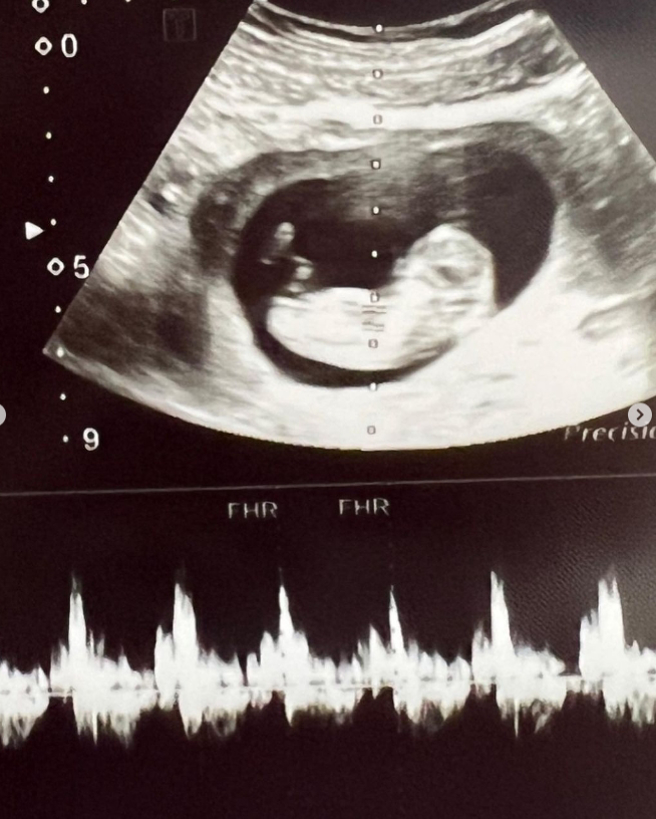

前职篮球星毛加恩与造型师老婆罗雯婚后1年就添丁,在2021年8月怀第2胎时,在孕期6个月时剧烈宫缩早产,女儿出生4天后因气胸严重撑不过急救。她昨日(12)深夜宣布好消息:「我又怀孕了!」

没想到上帝真的给了我这不可思议的礼物,对的,我又怀孕了!虽然这一胎一开始平安度过前12周,但前阵子又因为出血我必须躺着安胎,从一怀孕到现在我必须要自己打针,从一开始不敢打,到现在轻而易举,虽然又面临这些最怕遇到的状况,也偶尔还是会沮丧不安,但现在的我仍信心满满,因为我知道这一切都有神的美意,我也很享受这一切即便是需要躺着安胎。

我还有好一段孕期要走,我会努力的保护宝宝,希望他能住好住满,只要宝宝健康,什么打针吃药我都不怕,母爱的力量真的非常强大,虽然步步维艰,但希望这一次顺顺利利平平安安,宝宝跟我都一起加油!我相信这一次我可以的!